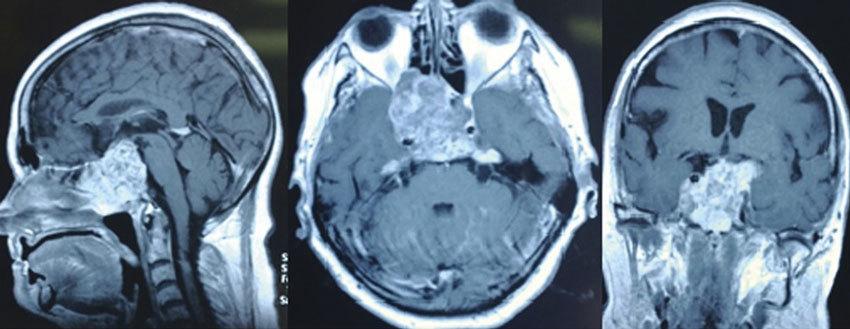

В большинстве случаев поводом для обследования становятся жалобы пациента на головные боли или неврологические нарушения. Ведущий метод диагностики — МРТ с контрастированием, достаточно точно характеризующая внутреннее строение новообразования и взаимоотношения с окружающими структурами.